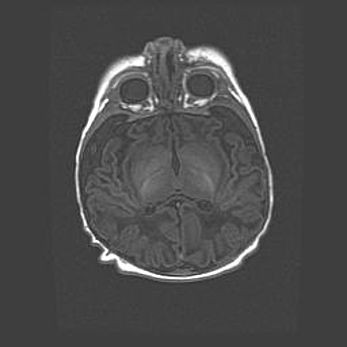

Лейкомаляция с кистозно-глиозной дегенерацией головного мозга.

Возраст: 2 месяца 25 дней

Вес: 6400 г

Окружность головы: 40 см

Срок гестации: 41 неделя

Лейкомаляцию относят к ишемически-гипоксическим повреждениям головного мозга, диагностируемым у новорожденных. При лейкомаляции в головном мозге обнаруживают очаги некроза, возникшие после тяжелой гипоксии и нарушения кровотока. В процессе морфогенеза очаги проходят три стадии: 1) развития некроза, 2) резорбции и 3) формирования глиозного рубца или кисты. Перивентрикулярная лейкомаляция (ПЛ) встречается примерно в 12% случаев среди новорожденных, обычно – у недоношенных детей, причем, частота ее зависит от массы, с которой младенец появился на свет. Наибольшее число малышей страдает лейкомаляцией, если масса при рождении 1500-2500 г.